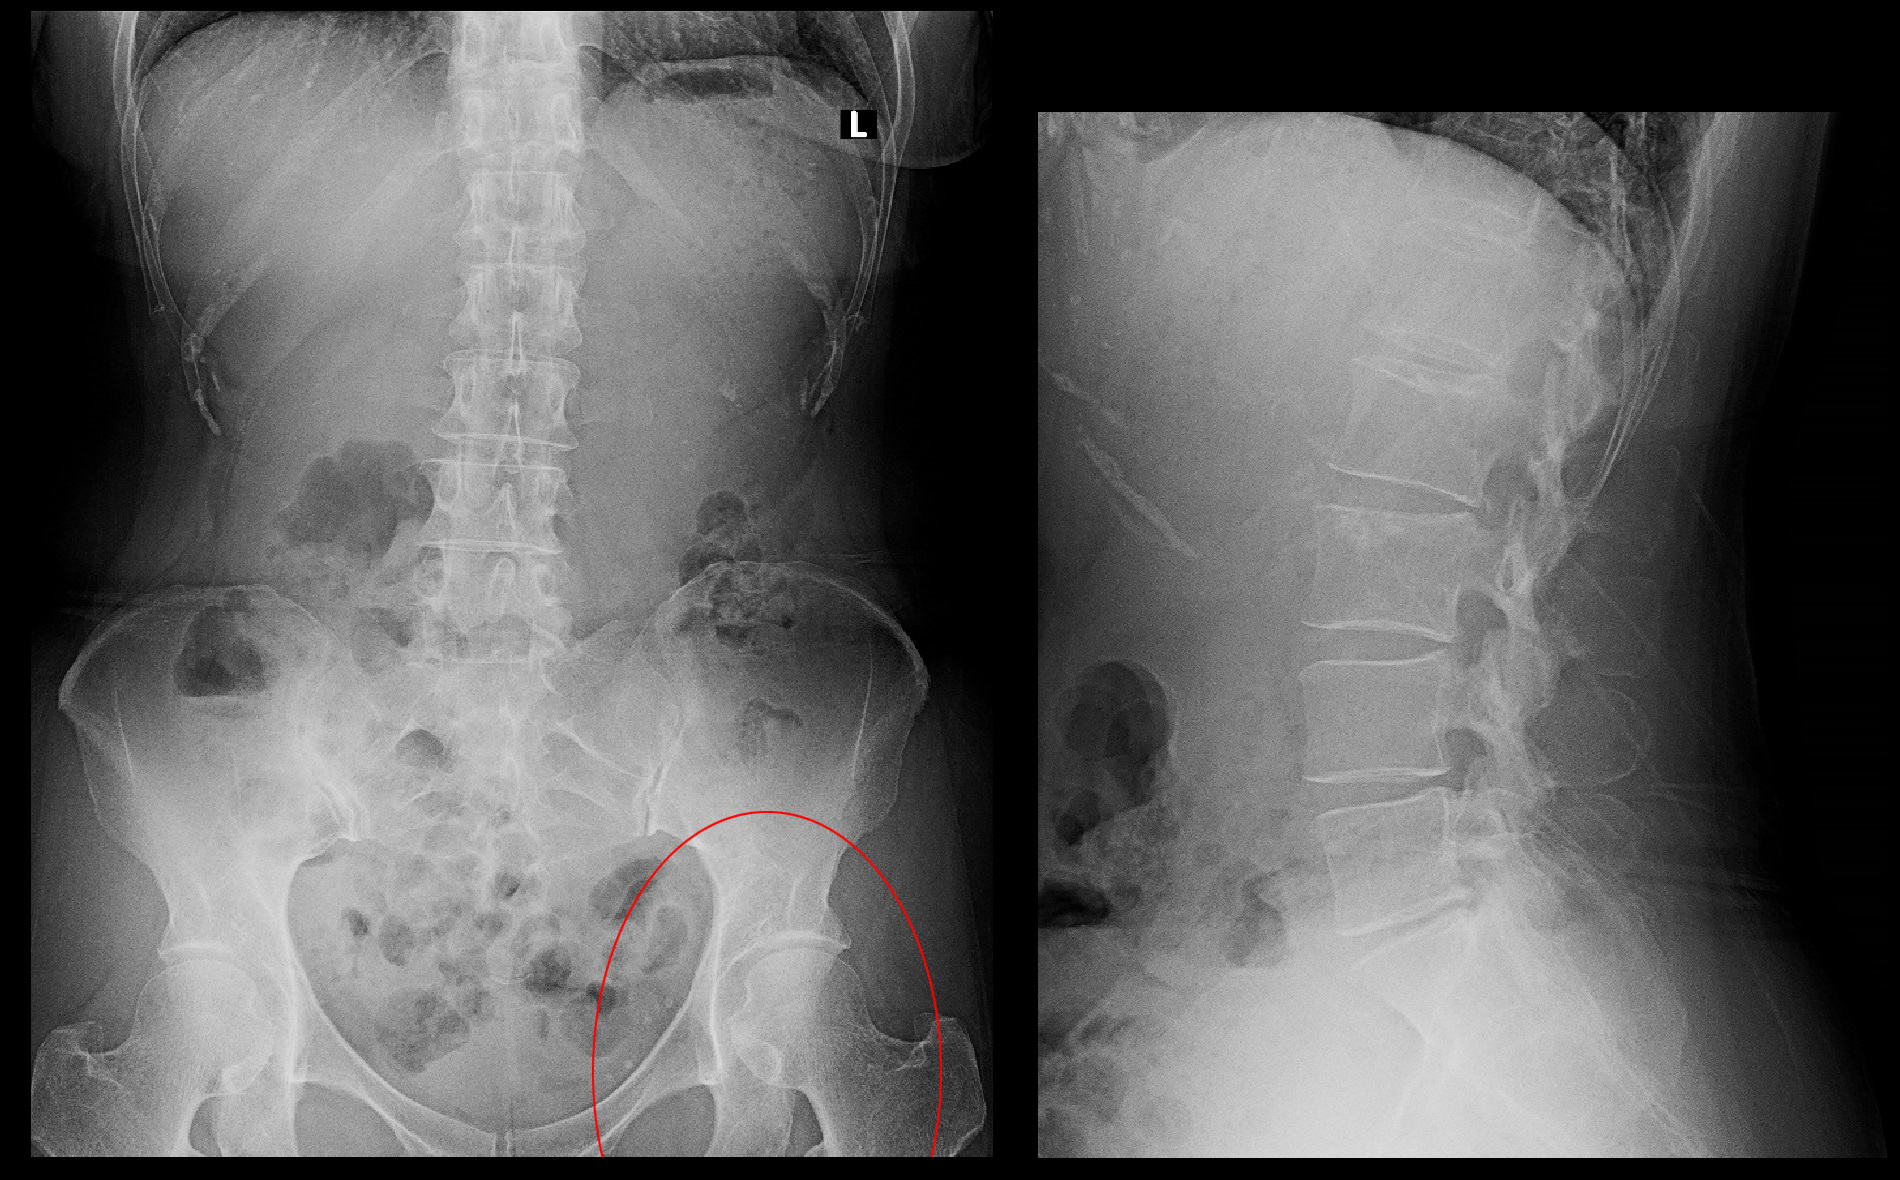

54才女 Xp1.jpg

腰椎レントゲン像は、L5S椎間板の狭小化を認める程度で年齢の割には加齢性所見は軽度であると評価できます。股関節MRI検査も行っていますが、異常所見は確認されませんでした。